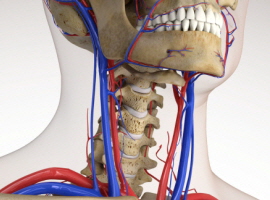

목 디스크는 목의 디스크(경추 디스크)에서 출현하는 질환으로, 경추 디스크 사이의 연골판이 터져 디스크 내부 물질이 경추 신경을 자극해 통증이나 저림증 등의 증상을 유발 해요. 목 디스크는 일상생활에서의 안 좋은 자세나 많은 운동, 부상 등이 이유가 되는 것이 될 수 있기도하고, 시간이 지날수록 발생 확률이 높아져요. 목 디스크의 증상으로는 목 부위의 통증, 팔의 저림, 근육 약화 등이 있으며, 증상이 난폭한 경우 수술 등의 치료가 필요할 수 있어요. 그리하나 대개의 경우 치료 없이도 시간이 지나면 증상이 호전되는 경우가 대부분입니다.

척수라는 중추 신경은 목뼈를 통과해 목 아래 감각과 운동 신경에 영향을 끼치기 때문에 목 디스크 증상들이 나타나면 신속하고 빠른 대처가 필요해요. 목디스크 치료형식으로 주로 초기 스탭에는 물리치료나 약물을 통해 대개의 환자들이 호전돼요. 그렇지 않다고 하면 신경 성형술과 차단술이라고 부르는 뼈주사 목디스크 치료방법을 이용하는데, 이 치료방법은 통증이 있는 신경 부위에 약물을 삽입하는 것입니다.